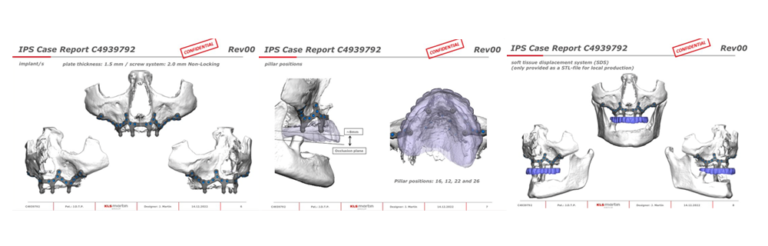

Modelos de planificación 3D para estructuras subperiósticas

Modelos 3D de CBCT de esqueleto facial par la planificación de Estructuras Subperiósticas.

Estructura Subperióstica con carga inmediata maxilar

Paciente con atrofia total del hueso del maxilar que precisa rehabilitación. Se le realizó tratamiento con estructura subperióstica y el mismo día se le colocaron unos dientes fijos provisionales sobre la estructura.